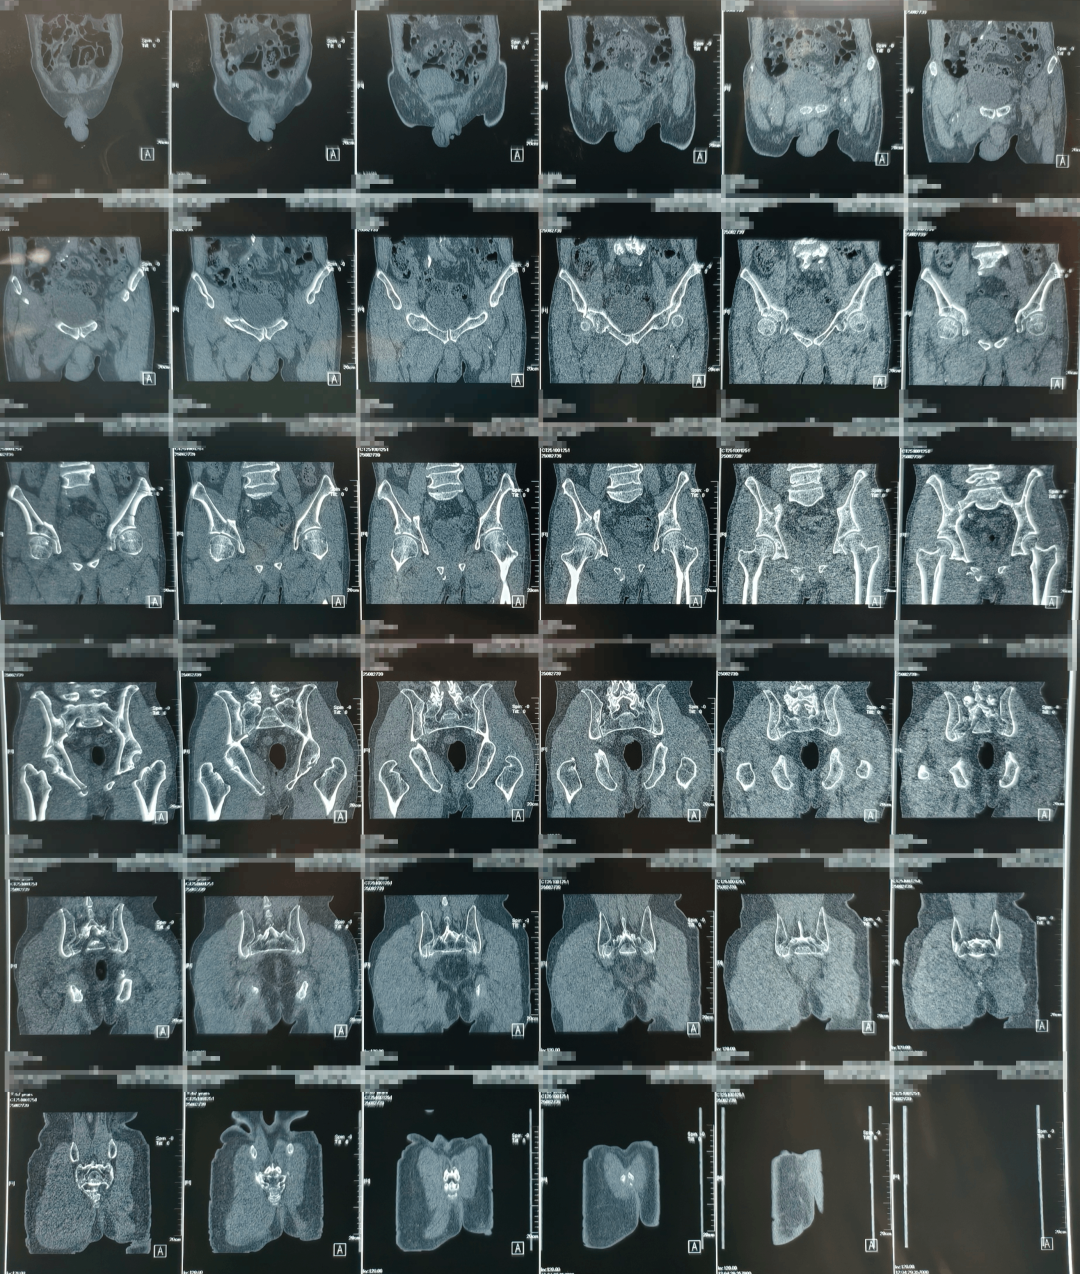

术前

团队通过三维影像重建,为患者量身定制手术路径,数据导入系统后生成个性化复位方案。

此次接受手术的七旬老人,因干活时不慎从自驾车摔落,导致全身多部位骨折,其中包括胸椎压缩性骨折、腰椎压缩性骨折、髂骨骨折、骶骨骨折、尾骨骨折、耻骨骨折、坐骨骨折。因骨盆结构复杂、周围血管神经密集,骨盆骨折素有“创伤之王”之称。面对患者骨盆多处骨折、血红蛋白偏低、传统手术可能带来较大创伤和出血风险等难题,贾长军主任团队果断选择借助最新引进的骨科手术机器人,制定个性化微创手术方案。